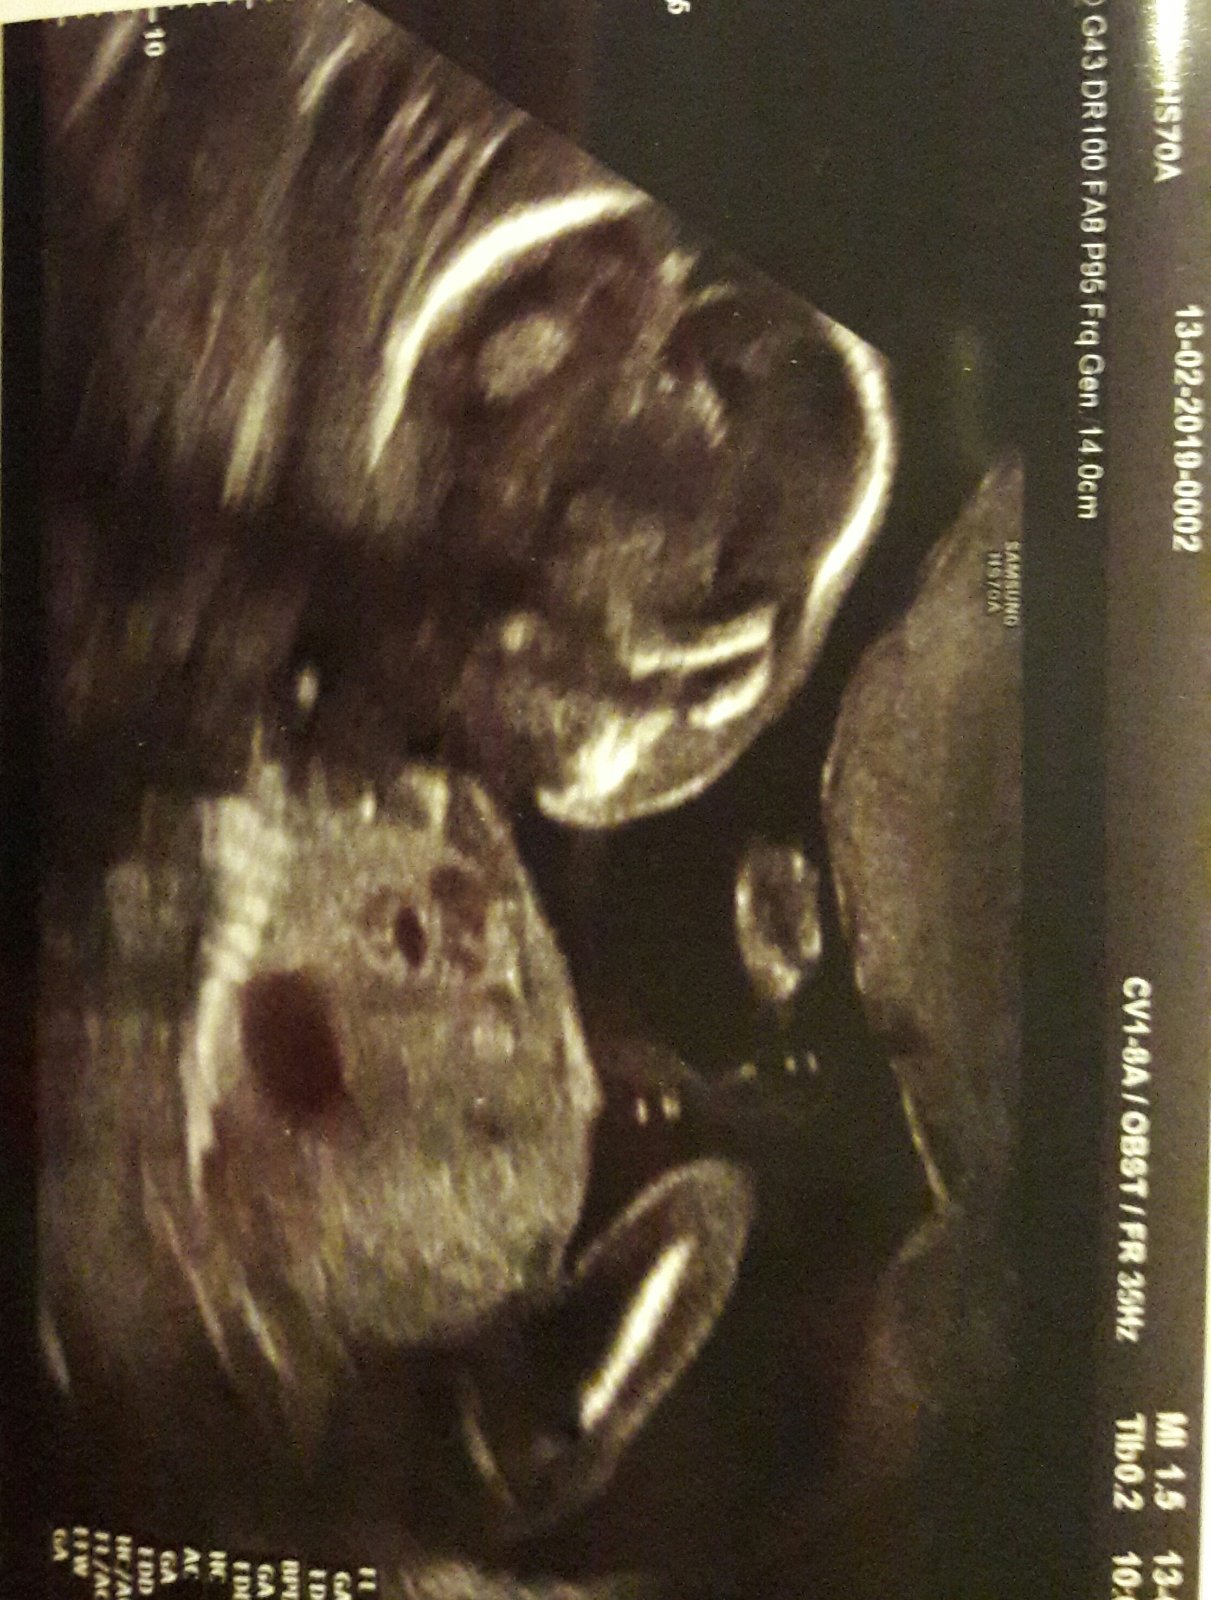

tak já byla dneska u dr, říkal že mimi velikostně odpovídá.. tluče mu srdíčko.. 19.2. jdu na další kontrolu a pak 21 odběry a 22 poradna a tam mi prý dá průkazku